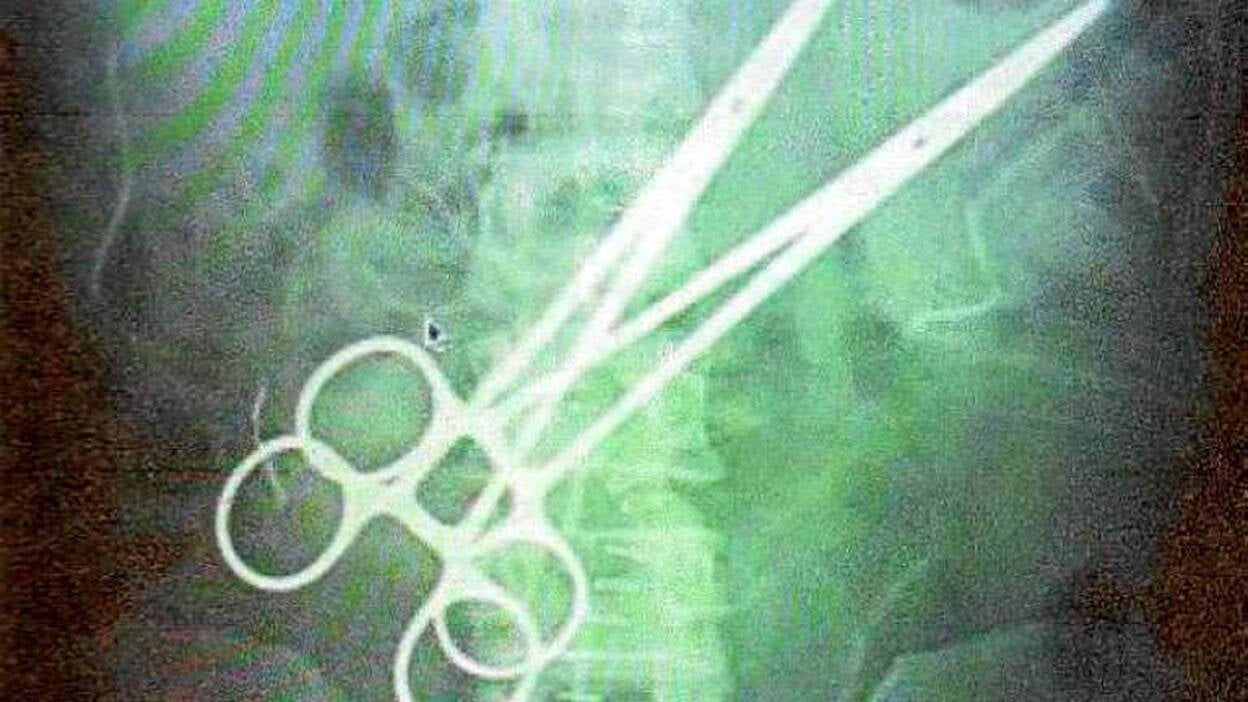

El médico que olvidó las pinzas en el estómago de un paciente en el Sur en 2011 no era especialista y se dejó el material en una segunda operación en la que intentaba arreglar una imprudencia previa, según las conclusiones del médico forense, que aprecia «impericia, imprudencia y negligencia». El médico del Sur de Gran Canaria que el 14 de octubre de 2011 se olvidó dos pares de pinzas en el estómago de un paciente cometió el descuido cuando intervenía al afectado por segunda vez para intentar subsanar un fallo en la primera operación, en la que había tratado de forma errónea una úlcera, según los médicos forenses Nelia Alegre y Fernando Borsani. El informe de los citados facultativos califica globalmente la actuación del médico que trató al ciudadano chino residente en Maspalomas Dong Y. L. de 38 años, como una «impericia» en la que concurrieron «imprudencia» y «negligencia» que se llevó a cabo con «inobservancia de reglamentos». Aprecian los peritos judiciales que ni en la primera operación (para tratar la úlcera de estómago) ni en la segunda (para intentar arreglar los daños generados al tratar la úlcera, en la que se dejaron las pinzas dentro del cuerpo) se solicitó el consentimiento informado del paciente, y agregan que el médico, A.A.C., «sólo está licenciado en medicina general, no como especialista en Cirugía Digestiva». Objeta el dictamen que aunque un médico general tenga los conocimientos suficientes para proceder a practicar de acto médico/quirúrgico de urgencia, «no puede ser ni actuar como el único responsable de un servicio o acto de tan envergadura o complejidad». El peritaje detalla que el cocinero Dong Y. L. acudió sobre las 15.30 horas del 14 de octubre de 2011 al servicio de urgencias del Hospital San Roque Maspalomas por dolor abdominal intenso. Se le diagnosticó una úlcera gastroduodenal y por el médico A.A.C. se le practicó una vagotomía, técnica que, dicen los forenses, ha caído en desuso desde que se descubrió que la mayoría de la úlceras tiene una etiología infecciosas. «También debemos decir que, aunque la intención del cirujano fue la de realizar una vagotomía troncular bilateral», informan los peritos judiciales, «ésta resultó fallida e incompleta»: no sólo se hallaron restos del vago izquierdo en la biopsia, sino que el paciente seguía con acidez, ardor, vómitos y dolor epigástrico. «Por lo tanto, entendemos que se produjo una actuación deficiente que produjo un daño evitable por descuido o impericia en la atención prestada», concluyen. Pero en esta primera intervención no sólo se consumó mal la vagotomía, sino que, sigue el informe, se provocó una hemorragia «a consecuencia del desgarro/rotura del bazo en la manipulación realizada en la primera intervención». Es al llevar a cabo esta segunda operación cuando el médico se olvida las pinzas dentro del paciente.